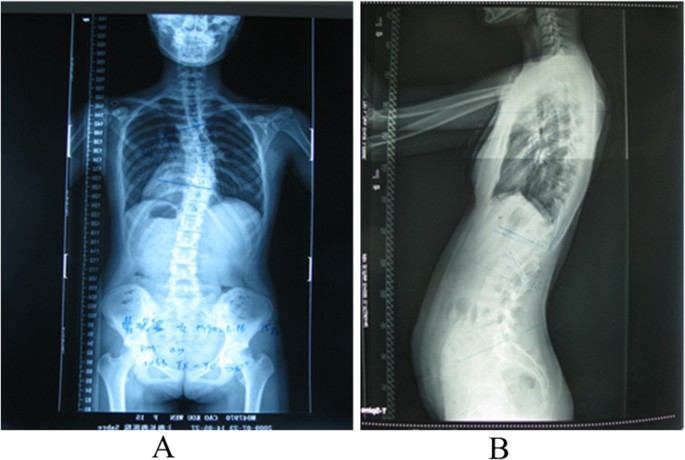

Измерение кифоза грудного отдела: Рентгеновские снимки